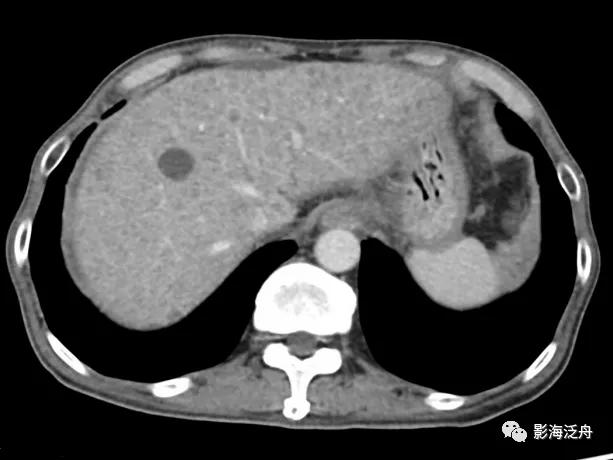

年轻女性,重度脂肪肝患者,平时喜食甜食及奶茶。

CT平扫上可见肝实质密度弥漫性减低,低于同层面脾实质密度(黄箭),肝内血管呈相对高密度影(红箭)。